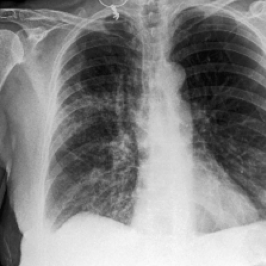

Waterbirds (Sagawa et al., 2020) is an image classification dataset where bird types are associated with a spurious background attribute (water or land). CelebA (Liu et al., 2015) is an image classification dataset, where hair color is an imbalanced attribute with respect to gender. MultiNLI (Williams et al., 2018) is a text benchmark of categorizing two sentences as entailing each other, contradicting each other, or neutral. The spurious correlation is between negation words like “never” and the “contradiction” label. CivilComments (Borkan et al., 2019) is a toxicity text classification dataset containing underrepresented demographic groups. CheXpert (Irvin et al., 2019) is a large-scale medical dataset of chest radiographs with rare pathologies, especially amongst certain minority groups.